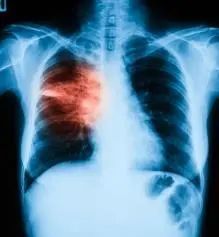

“假感冒”之二:大叶性肺炎

主要由肺炎链球菌引起,会出现高烧、咳嗽、打寒战等类似感冒症状。临床上这种病最易在青壮年身上发生,他们往往觉得自己身强体壮,把该病早期出现的咳嗽、多痰和发热等症状看成普通感冒,耽误了治疗。

大叶性肺炎的一个重要特征就是患者都会发热,并且在进行x光检查时,肺部可见明显的实质性变化。受寒、疲劳、醉酒、淋雨引起的感冒,都可能诱发大叶性肺炎,因此避免受寒及过度疲劳是很有效的预防措施。